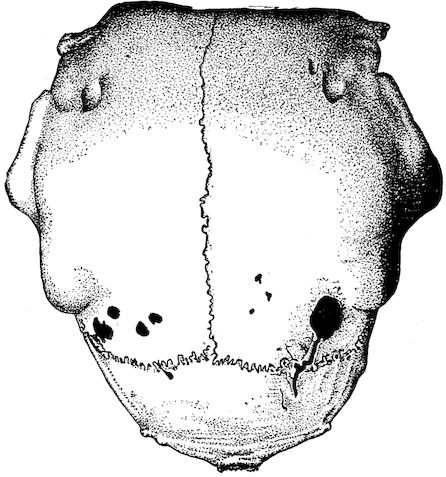

Fig. 8.—Transverse section through the middle region of the face in a pig suffering from osseous cachexia.

18In the final stages, the bones may be cut with a knife, and a time arrives when bony tissue seems completely to have disappeared; thus, as shown in Fig. 8 herewith, it was possible to cut the entire head of a pig into thin slices without the slightest difficulty. All parts of the head had been affected by the softening change.

From the chemical point of view, the diminution in mineral salts and in phosphate of calcium has long been recognised, but the degree of this change varies according to the phase. In human beings the proportions have been estimated as follows: Normal bone, 50 to 80 per cent. of phosphate of calcium; bone in persons suffering from osteomalacia, 5 to 20 per cent. of phosphate of calcium. The changes in the ossein have not been carefully studied. We only know that histologically the ossein becomes fibrillar, and that chemically it no longer retains its normal composition.

Fig. 4.—Deformity of the face in the horse shown in Fig. 2.

The flat bones are particularly liable to this change, which is common to domesticated animals. The bones of the head are the first to suffer; later those of the pelvis. The lower jaw becomes swollen, particularly about the centre of the branches which may attain three, four, or five times, their normal thickness.

The depression in the submaxillary space disappears. The upper jaw undergoes similar changes, becoming deformed and thickened until the cavities of the sinuses and the hollow appearance of the palate are lost, while the face is so changed that it cannot be recognised as that of a horse, goat, etc.

The molar teeth are almost buried, their tables alone being visible at the bottom of a depression, the edges of which rise above the neighbouring parts (pig).

Mastication is clearly impossible, the jaws appear paralysed, the muscles powerless, and only swallowing is possible, a fact which explains why life is only prolonged to this stage in animals which can be fed with a spoon or bottle (pigs and goats). The bones of the cranium, although greatly changed in texture, are always less deformed than those of the face.

The changes are such that it is often easy with a mere post-mortem knife to cut the head completely in two. Osseous tissue, properly so-called, has disappeared.